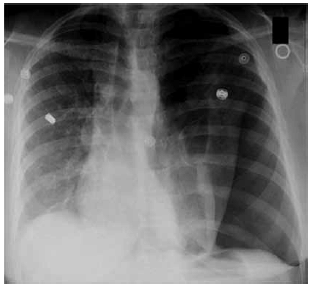

Homem, 55 anos, encontra-se internado para tratamento da covid-19. No décimo sexto dia da doença, tendo sido extubado há 48 horas, recebeu alta para a enfermaria, onde permaneceu em uso de cateter nasal de O2 2 L/min. Encontra-se em uso de enoxaparina 40 mg, metilprednisolona 40 mg/dia e esomeprazol. Antecedentes pessoais: tabagista, com carga tabágica de 60 maços-ano, e obeso. Durante a noite, apresentou episódio de dispneia súbita, associada à dor torácica à esquerda, sendo necessária máscara de Venturi 50% para manter SpO2 em torno de 91%. Neste momento, o exame clínico do paciente apresentava os seguintes achados relevantes: PA = 110 x 70 mmHg, FC = 110 bpm, SpO2 = 92%, FR = 26 ipm; ausculta pulmonar abolida em hemitórax esquerdo, com estertores difusos em hemitórax direito.

A radiografia de tórax encontra-se a seguir.

Assinale a alternativa que apresenta a conduta correta, neste momento.